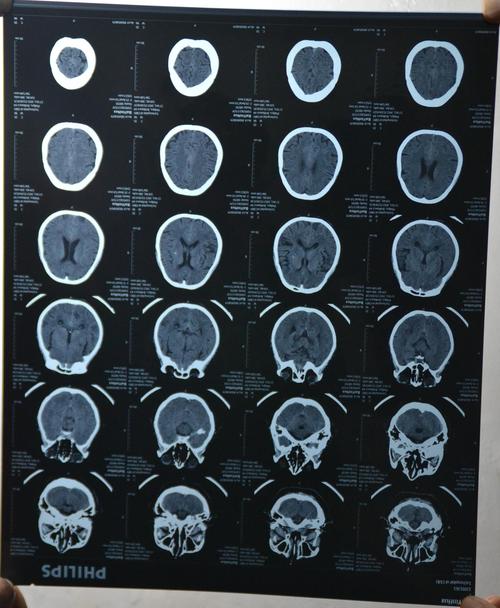

简明又详细的头部ct读片详解!

脑部CT图像

脑部ct图片

脑部ct怎么看图解

脑ct图片讲解

新手看脑部ct片图解

头ct部位图谱